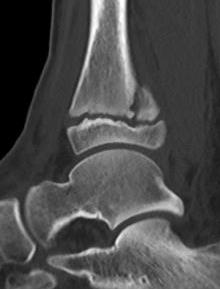

Triplanar Fracture

Definition

Fracture in coronal, sagittal and transverse planes

- crosses epiphysis

- passes through growth plate

- extends into metaphysis

Xray

AP xray: Salter-Harris type III / Tillaux

Lateral xray: Salter-Harris Type II

CT

Coronal images: Salter-Harris type III

Sagittal images: Salter-Harris type II

Axial images: 3 point star